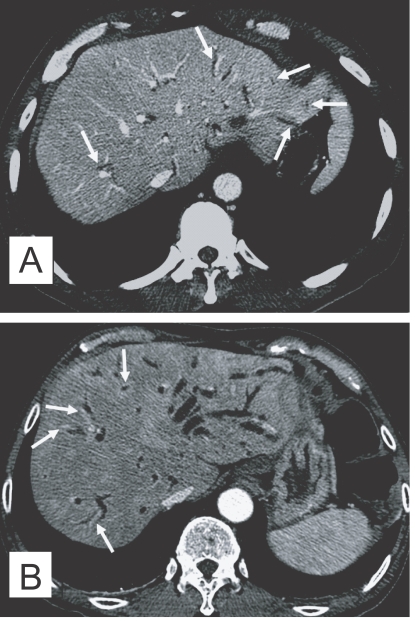

The CT finding of clonorchiasis is diffuse dilatation of the peripheral intrahepatic bile ducts, without dilation of the larger bile ducts or extrahepatic ducts (Fig. 3A). This finding is known to be the pathognomonic findings of clonorchiasis (Lim, 1990), however, it is also observed in cured infection.

In contrast to sonography showing an increased echogenicity of the ductal wall, CT failed to show thickening of the bile duct wall (Choi et al., 1989). A recent experimental study, however, suggested that an active infection could be differentiated from cured clonorchiasis by using the periductal enhancement with the thickened bile duct walls on dynamic contrast-enhanced CT (Lee et al., 2003). The contrast-enhanced CT visualized a characteristic finding, transient hepatic attenuation differences (THAD). The finding was interpreted as an outcome of new vascularization in the thickened bile duct wall, which disappeared after cure of clonorchiasis (Fig. 3B). They also asserted that some adult worms were demonstrated on their thin-section CT scans (Lee et al., 2003).

MR imaging has been used in diagnosis of various diseases of the biliary system, and MR cholangiography is a relatively new non-invasive imaging modality for evaluation of the biliary pathology. MR imaging can show the characteristic findings of clonorchiasis with diffuse, mild dilation of the small intrahepatic bile ducts, particularly in the periphery of the liver (Choi et al., 1998). According to a recent study, MR cholangiography also found "too many intrahepatic ducts" sign in 62% (16 of 26) of patients with clonorchiasis (Jeong et al., 2004). Periductal enhancement was more frequently seen on MR imaging, compared to CT, due to a higher spatial resolution of the soft tissue (Fig. 4). The filling defects representing worms were elliptical, irregular shaped, and hypointense lesions on the T2-weighted images and MR cholangiography.

Fig. 3

Contrast-enhanced CT findings of the liver in clonorchiasis patients. A. A 52-year-old man, who underwent liver transplantation in China 1 month before CT examination, shows diffuse and mild dilatation of the peripheral intrahepatic bile ducts (arrows). The transplanted liver had been infected with C. sinensis. B. Periductal enhancement (arrows) with the thickened bile duct walls on hepatic arterial phase of dynamic study, which possibly represents active infection, in a 61-year-old man.

Fig. 4

MR findings of the liver in clonorchiasis patients. A. MR cholangiography in a 58-year-old man, who underwent cholecystectomy 10 year ago, showing diffuse and uniform dilatation of the peripheral intrahepatic bile ducts. B. Periductal enhancement of mildly dilated intrahepatic bile ducts (arrows) on hepatic arterial phase of dynamic study of gadolinium-enhanced echo fast gradient echo 3D (TR/TE, 7/2) transverse image, which possibly represents active infection, in a 60-year-old man (Courtesy of Dr. Yong Yeon Jeong, Gwangju, Korea).

Fig. 3 Contrast-enhanced CT findings of the liver in clonorchiasis patients. A. A 52-year-old man, who underwent liver transplantation in China 1 month before CT examination, shows diffuse and mild dilatation of the peripheral intrahepatic bile ducts (arrows). The transplanted liver had been infected with C. sinensis. B. Periductal enhancement (arrows) with the thickened bile duct walls on hepatic arterial phase of dynamic study, which possibly represents active infection, in a 61-year-old man.

Fig. 4 MR findings of the liver in clonorchiasis patients. A. MR cholangiography in a 58-year-old man, who underwent cholecystectomy 10 year ago, showing diffuse and uniform dilatation of the peripheral intrahepatic bile ducts. B. Periductal enhancement of mildly dilated intrahepatic bile ducts (arrows) on hepatic arterial phase of dynamic study of gadolinium-enhanced echo fast gradient echo 3D (TR/TE, 7/2) transverse image, which possibly represents active infection, in a 60-year-old man (Courtesy of Dr. Yong Yeon Jeong, Gwangju, Korea).